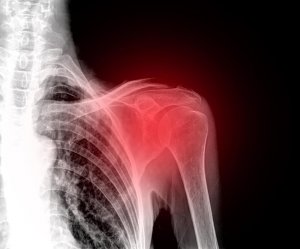

Біль у плечі є дуже незручним, тому що плечовий суглоб дає змогу ефективно взаємодіяти з навколишнім світом. Є різні види травм, які можуть викликати біль, набряк та нерухомість. Також у вас може виникнути хронічний набряк, якщо ви не отримаєте медичне лікування.

Перш за все варто знати, що біль у плечі виникає частіше, ніж ви думаєте. Вам потрібно звернутися до лікаря у випадках вивихів та переломів. Ці дві ситуації, як правило, є результатом травми в цій ділянці.